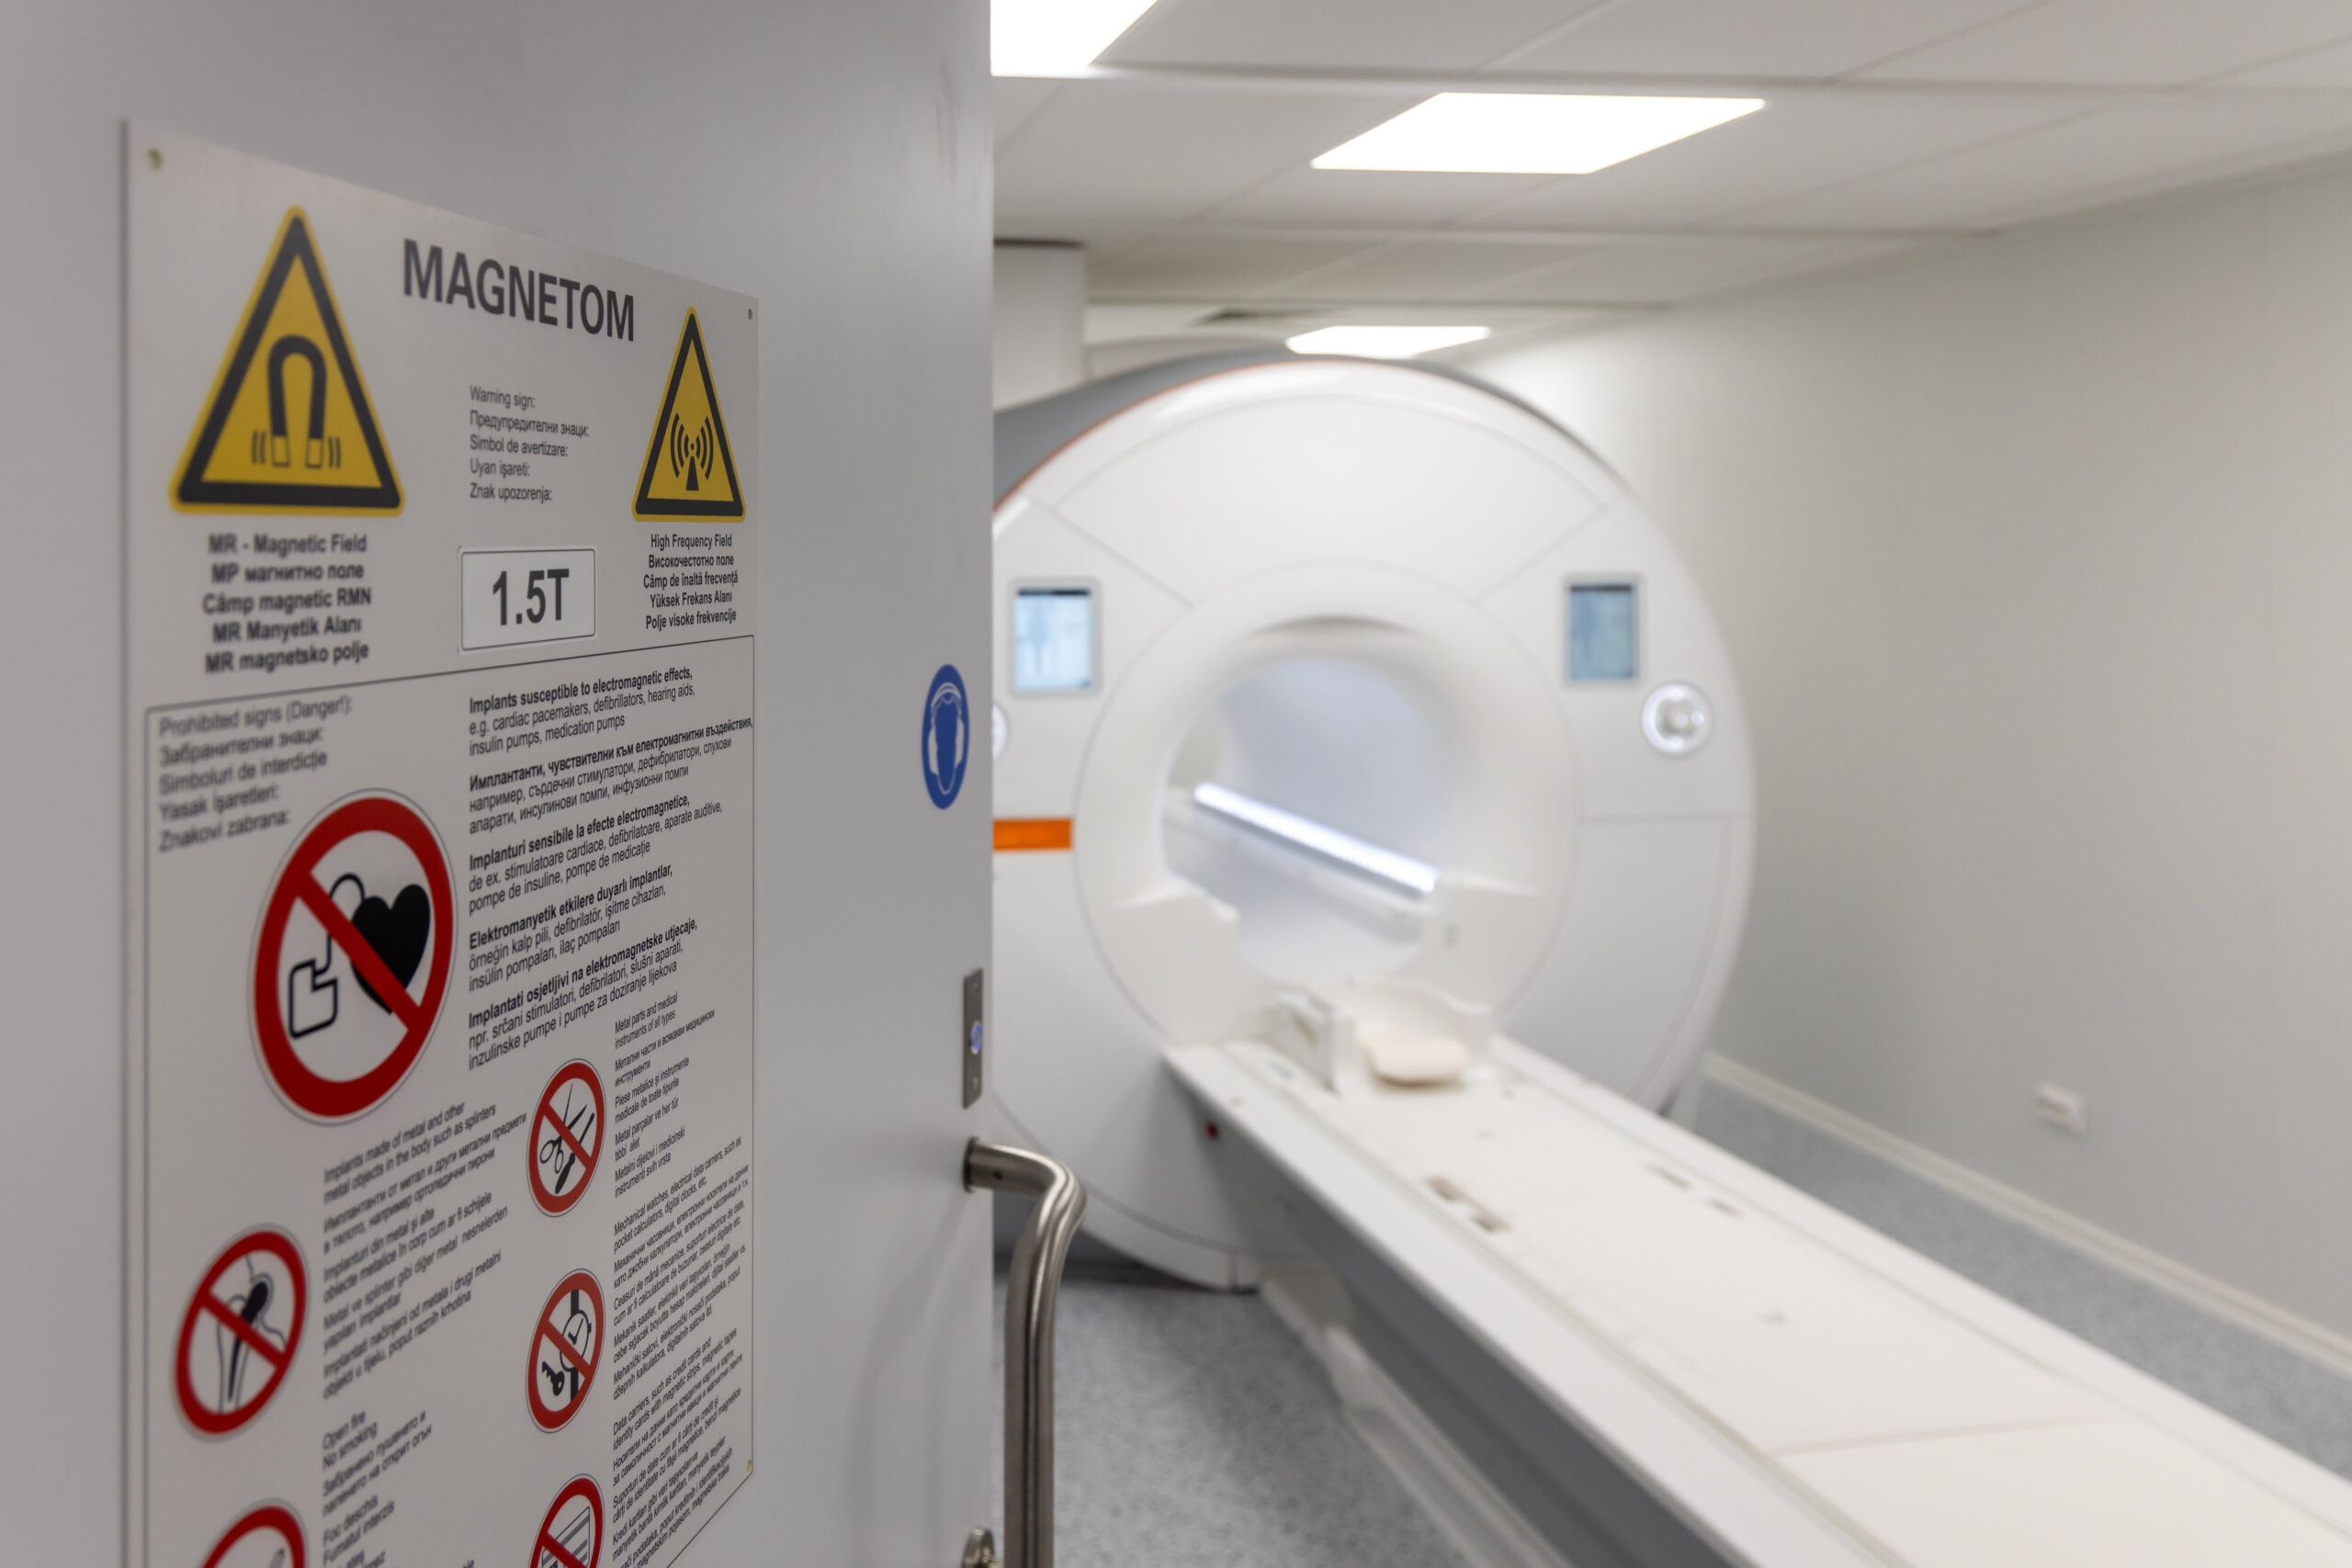

MRI検査を受けることになったときに、「歯のインプラントが入っているけど、本当に問題ないのかな?」と不安に感じていませんか。

結論からお伝えすると、現在のチタン製インプラントであれば、MRI検査はほぼ100%受けられます。チタンは磁石に反応しないため、MRIの強い磁場でも安全です。

本記事では、MRIが受けられるケースと例外や事前に確認すべきポイント、検査当日の伝え方、なぜ金属がMRIで問題になるのかをわかりやすくまとめていきます。

結論:デンタルインプラント治療後でもMRIはほぼ100%受けられる

結論、インプラント治療後でもMRI検査は問題ありません。以降では、なぜ問題ないのか、注意点も踏まえて紹介します。

なぜMRI検査では「金属=危険」と言われるのか?その理由をわかりやすく説明!

MRI検査では、非常に強い磁場(磁石の力)と電波を使います。そのため、金属の種類によっては「磁場に引っ張られる」「熱を持つ」「画像が乱れる」などが起こることがあります。

MRIが「金属に注意」と言われる理由

MRI検査で金属が危険だといわれる理由は、主に次の3つです。

- 磁場に引っ張られて動くリスク(磁力に反応する金属)

- 金属が熱を持つ可能性(電波による発熱)

- 画像が黒く歪む(アーチファクト)